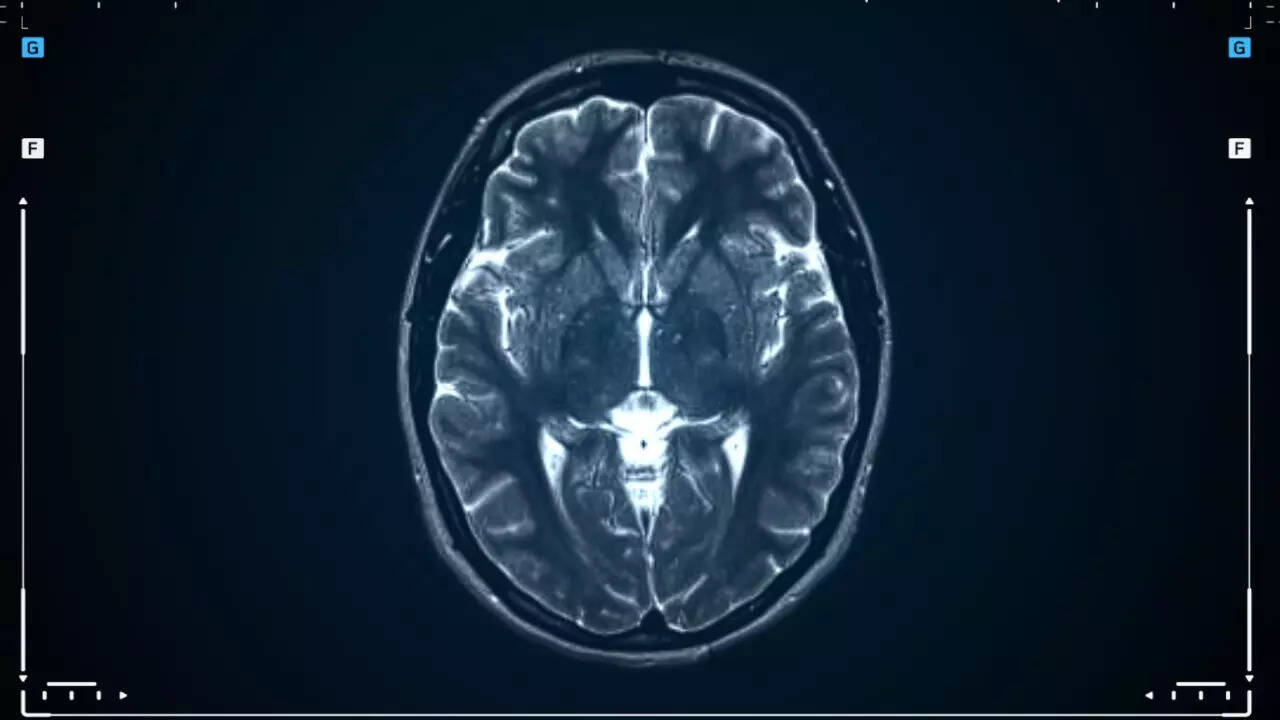

COVID infection triggered deadly brain disease in man?

While there has been enough evidence about COVID-19 triggering and worsening neurodegenerative diseases, a recent case was highlighted by the American Journal of Case Report discovering a correlation between COVID and a fatal brain disorder. The case in discussion was about a man aged 62 admitted to Mount Sinai Queens Hospital Center, New York. The man was infected with COVID-19 when he was admitted and along with this, he had been undergoing progressive dementia, myoclonus, and difficulty walking. His neurological condition worsened and ultimately resulted in his death. The death was suspected due to Prion Disorder(PrD), a deadly brain disease, upon contracting COVID.

Despite extensive diagnosis of the man, including brain imaging, all results were unremarkable. However, the clinical suspicion persisted, leading to the ordering of CSF protein 14-3-3 testing for the diagnosis of Creutzfeldt-Jakob disease (CJD)- which belongs to a group of diseases known as prion disorders. It returned with a positive result.